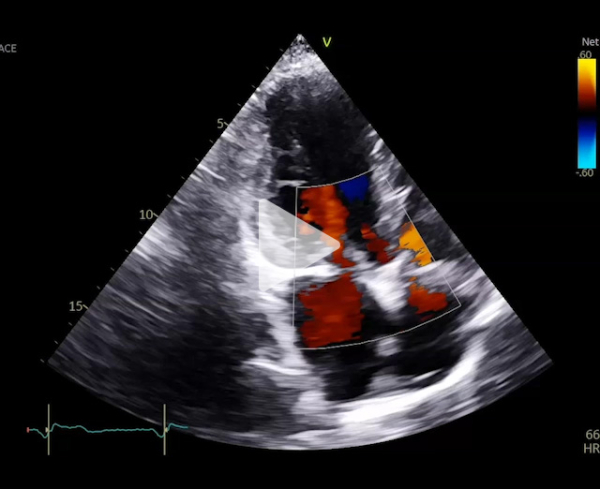

Nouvelle évaluation globale : ETT - ETO

Vidéo 1

- Ventricule gauche dilaté 87 ml/m2, FEVG 79%.

- Oreillette gauche dilatée 55 ml/m2

- Valve mitrale : plastie mitrale sur valve barloïde, insuffisance mitrale de grade 3

- Restriction au niveau de P3

- SOR 30 mm2, VR 54 ml, PISA 8 mm

- Rapport ITV 1,8, onde E 1,8 m/s

- Pas de reflux dans les VP

- Gmoy 6 mmHg

- Fonction ventriculaire droite altérée

- Forte probabilité d’HTP